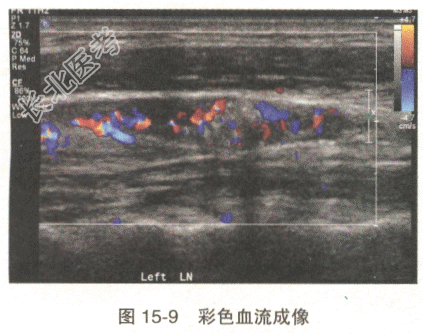

患者,女性,45岁。左颈部触及结节来诊。超声检查示左颈中部见一淋巴结,其声像图表现见图15-8、图15-9。

- 多项选择题1.对于该淋巴结的超声,叙述准确的是

A、中高回声团内见多个点状强回声

B、皮质内见中高回声团

C、髓质增厚,内见中高回声团

D、CDFI示中高回声区血流信号增多,分布不规则

E、髓质变薄,皮髓分界欠清

F、CDFI示淋巴结内血流分布规则,呈放射状

G、中高回声团边界不清